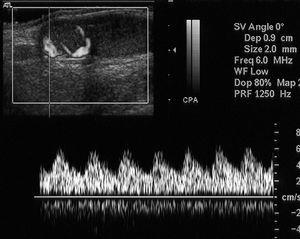

Un niño de 3 años sin antecedentes personales ni familiares de interés presenta una tumoración intraescrotal izquierda, asintomática, detectada por su pediatra en un examen físico rutinario. La exploración física evidencia testículos intraescrotales, de tamaño y consistencia normal, y una tumoración redondeada de 1 cm de diámetro, por encima del testículo izquierdo, bien delimitada, móvil, no dolorosa a la palpación y de consistencia similar al testículo. El resto de la exploración física no detecta hallazgos patológicos. Se realiza una ecografía y una eco-Doppler testicular que muestra una masa intraescrotal izquierda, extratesticular, homogénea redondeada de ecogenicidad y vascularización similar al testículo homolateral, sugestiva de tejido esplénico ectópico (fig. 1). La ecografía abdominal no detecta hallazgos patológicos. El hemograma, la bioquímica y la coagulación son normales. Se indica la realización de intervención quirúrgica para confirmar la sospecha diagnóstica, encontrándose una tumoración extratesticular, encapsulada, unida al polo superior del testículo izquierdo por un pedículo vascular (fig. 2). No se observa cordón o banda de tejido unida a la tumoración que se dirija y penetre a la altura del orificio inguinal externo. No existe persistencia del conducto peritoneo vaginal y el aspecto macroscópico del testículo y epidídimo izquierdo es normal. Se realiza la exéresis de la masa en su totalidad. La recuperación ocurre sin incidencias, y se le da el alta al niño a las 24 h del procedimiento. El estudio anatomopatológico de la tumoración confirma la sospecha diagnóstica de tejido esplénico ectópico; se trata de una fusión esplenogonadal discontinua.

Figura 1. Ecografía y eco-Doppler: masa intraescrotal y extratesticular de ecogenicidad y vascularización similar al testículo.

Debido a su rareza, el diagnóstico de sospecha preoperatorio ha sido realizado en pocas ocasiones 18. Actualmente gracias a la ecografía y eco-Doppler esta anomalía se diagnostica preoperatoriamente con mayor frecuencia 17,19. La ecografía demuestra la localización intraescrotal de una masa extratesticular homogénea, bien encapsulada, de igual ecogenicidad que el testículo normal 18,20. La demostración ecográfica de la FEG continua consiste en un proceso tubular que conecta el polo superior del bazo, hacia el canal inguinal, hasta el polo superior del testículo izquierdo. La tracción del testículo genera movimientos en el polo superior del bazo que se ven en una ecografía 10. Algunos autores han utilizado la gammagrafía para identificar el tejido esplénico ectópico 12.